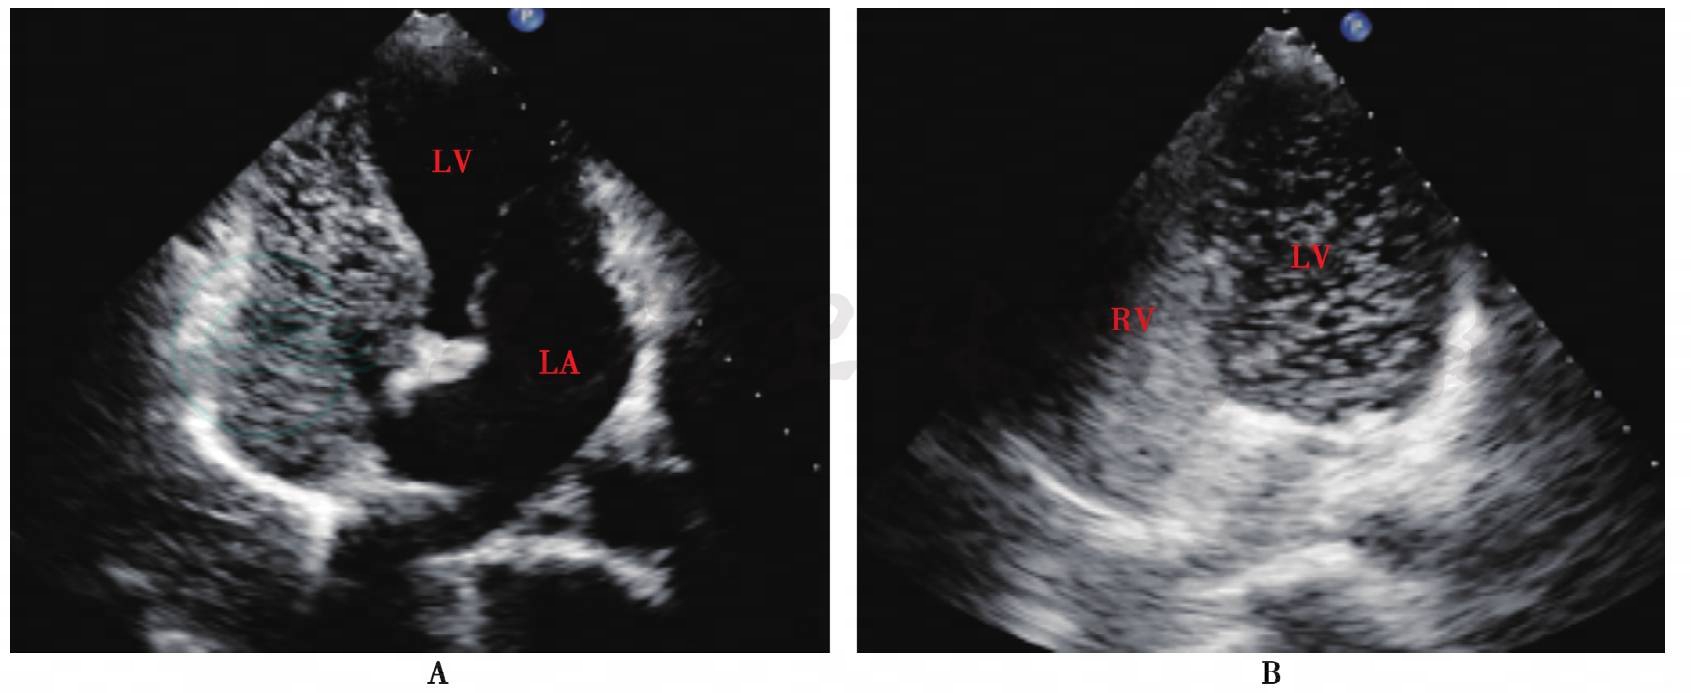

入院后给予营养神经、抗血小板聚集、改善肌张力等对症支持治疗。进一步完善影像学检查:全脑血管造影示左侧额顶叶大片血管染色缺血区(软化灶区域)。胸部CT示双肺下叶后底段少许炎性病灶。经胸超声心动图示各房室大小基本正常;房间隔中部薄弱,向右心房呈瘤样膨出16mm,基底宽25mm,瘤壁后上探及破口直径7mm,心房水平少量左向右分流;少量三尖瓣反流,诊为“先天性心脏病,房间隔膨胀瘤伴破口”(图1)。

图1 第一次经胸超声心动图

A:房间隔膨胀瘤伴破口;B:心房水平左向右分流